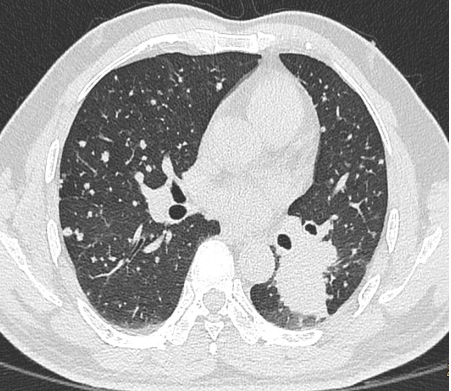

我们知道,辐射是很多人担心的问题之一。飞利浦Incisive AI CT拥有不限体型、不限部位的临床化低剂量成像,大幅抑制噪声的同时提高图像对比度,保障图像质量满足临床诊断要求。

▲ 肺内结节、无处隐藏